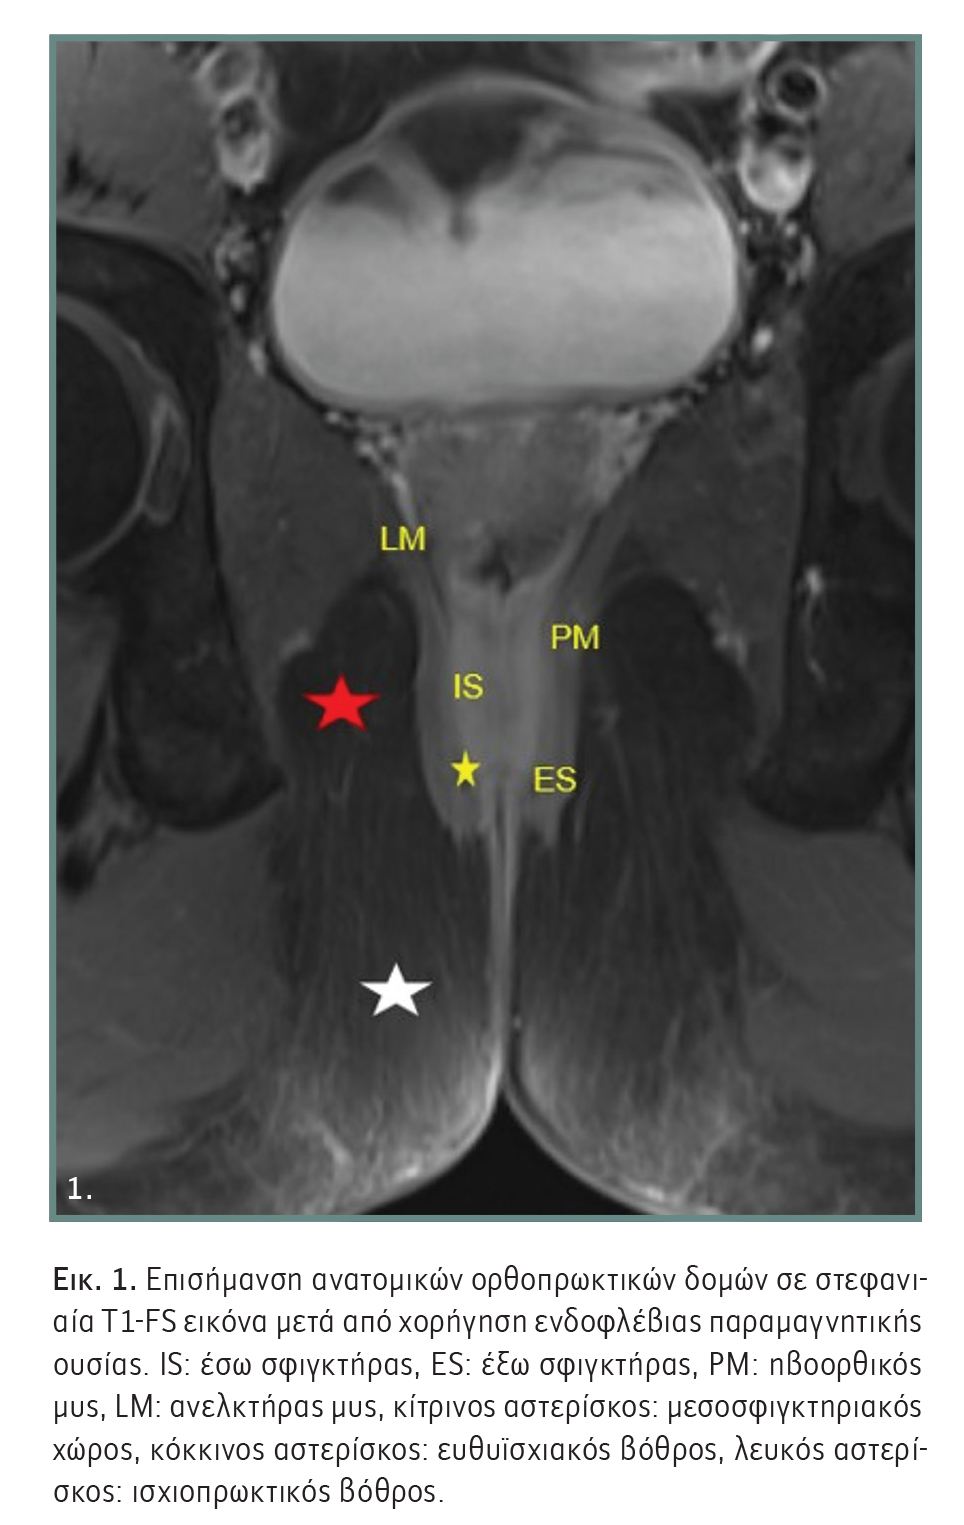

Η σωστή γνώση της ανατομίας του συμπλέγματος των σφιγκτήρων του πρωκτού και των επιχώριων δομών είναι ζωτικής σημασίας για την ερμηνεία των απεικονιστικών ευρημάτων. Το πρωκτικό κανάλι έχει μήκος 2-5 εκατοστά και περιβάλλεται από δύο σφιγκτηριακούς μύες, τον έσω και τον έξω σφιγκτήρα. Ο έσω σφιγκτήρας είναι η κατώτερη προέκταση του έσω κυκλικού λείου μυός του ορθού και είναι κυρίως υπεύθυνος του ακούσιου πρωκτικού ελέγχου. Ο έξω σφιγκτήρας αποτελείται από γραμμωτό σκελετικό μυ, ο οποίος εφάπτεται προς τα άνω τόσο με τον ανελκτήρα όσο και με τον ηβοορθικό μυ και είναι κυρίως υπεύθυνος για τον εκούσιο έλεγχο.

Σε απόσταση περίπου 2 cm στον πρωκτικό σωλήνα βρίσκεται η οδοντωτή γραμμή, στις αδενικές κρύπτες της οποίας εδράζονται οι πρωκτικοί αδένες. Οι αδένες εντοπίζονται κυρίως εντός του μεσοσφιγκτηριακού χώρου ή του έσω σφιγκτήρα (Εικόνα 1). Η λειτουργία των αδένων αυτών είναι η παραγωγή βλέννας, η οποία επαλείφει τα κόπρανα και διευκολύνει την αφόδευση. Η φλεγμονή και αποστηματοποίηση των αδένων αυτών, λόγω διείσδυσης μικροβίων ή απόφραξης του εκφορητικού τους πόρου, αποτελεί την κυριότερη αιτία ανάπτυξης του αποστήματος. Το περιεδρικό απόστημα θεωρείται οξεία εκδήλωση και το περιεδρικό συρίγγιο μια χρόνια κατάσταση της ίδιας νόσου.